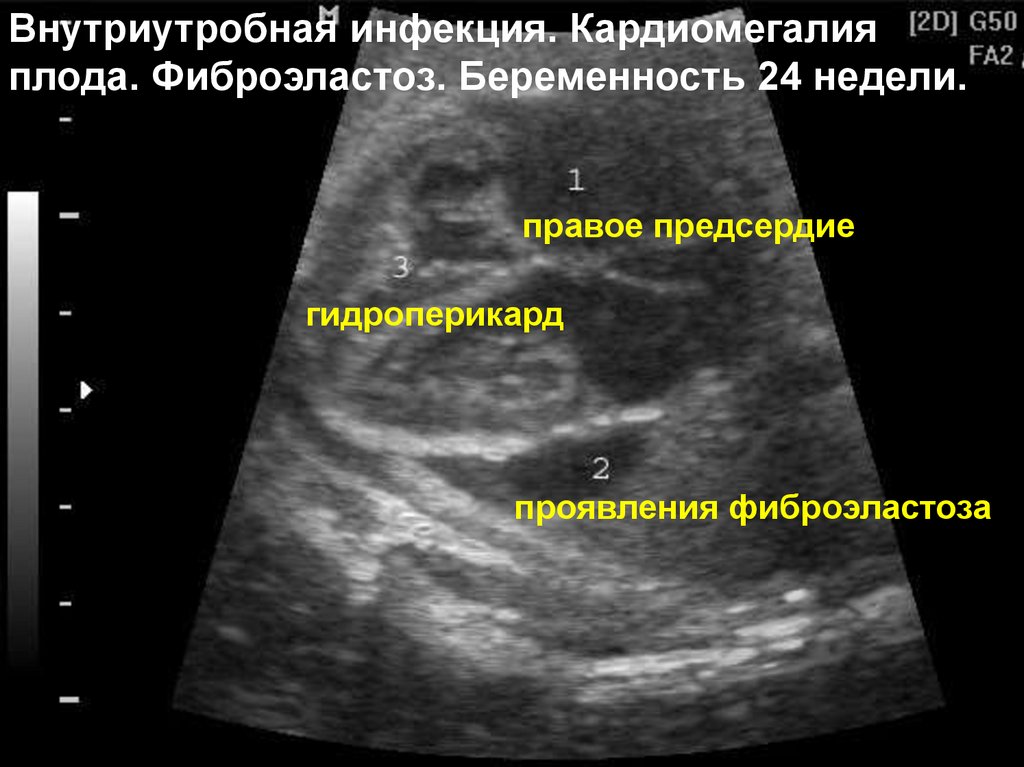

Внутриутробная инфекция. Кардиомегалия

плода. Фиброэластоз. Беременность 24 недели.

правое предсердие

гидроперикард

проявления фиброэластоза